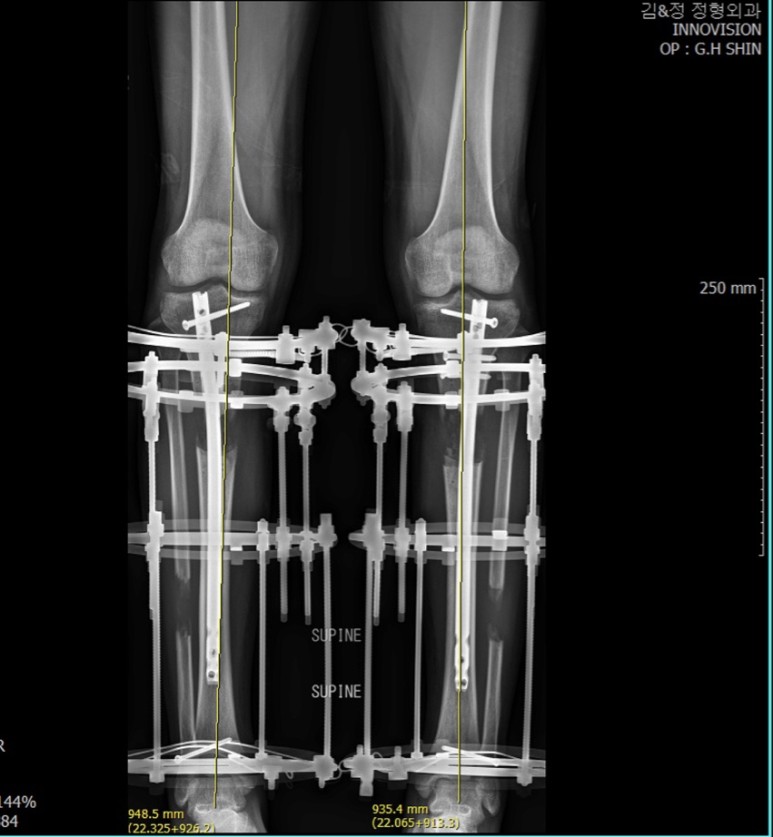

오늘 키 수술 재활, 소요시간에 대해서 글을 써 올려드렸었는데 이 부분에 대해서 할 이야기가 많고 환자분들이 가장 궁금해하시는 부분이라 종아리 속성연장수술을 받게 되면 얼마큼의 시간이 필요한지 한번 알려드려보고자 합니다.

일상 복귀: 목발을 2-3주 사용 가능하며, 환자분에게 남아있는 불편감은 있으나, 회사를 다니거나 학교를 다니는데 큰 지장이 없는 상태로 정해봅니다. 걷거나 할 때 까치발이 남아 있거나 발목과 무릎에 통증이 약간씩 남아 있는 경우가 있을 수 있지만, 주변 사람들은 느낄 수 없는 정도일 때 직장과 학교생활이 가능하다고 할 때, 그 시기까지 종아리 속성연장 후 필요한 시간을 정리해보면

일단 먼저 설명드려야 되는 부분이, 5-6-7-8센티는 필요한 기간이 아주 정비례로 늘어나는 것이 아닙니다. 연장 목표가 일정 부분 이상 올라가게 되면, 더 많은 소요기간이 필요하게 됩니다. 1센티 연장에 1달의 시간이 필요하다고 아주 대략적으로 그리고 약간 여유 있게 계산해볼 수 있는데요, 6센티를 연장하고 일상생활로 돌아가는데 6개월의 계산이 나오지만 사실상 5개월정도의 시간이면 일상생활을 시작하게 되고, 4개월반정도 필요한 경우도 있습니다.

키 수술을 받으시는 남녀 환주들 간에 편균 키의 차이가 있고, 환자 분마다 재활 상태의 차이가 있을 수 있어서 약간의 기간 차이가 있을 수 있습니다. 수술 전 키가 150cm인 여자 환자분이 수술 전 키가 167cm인 남자 환자와 같은 연장 스케줄로 가는 건 무리가 있을 수 있습니다. 이 부분을 고려해야 하며, 의료진과 충분한 상의가 필요하며, 적절한 연장 스케줄을 계획하는 것이 중요합니다.